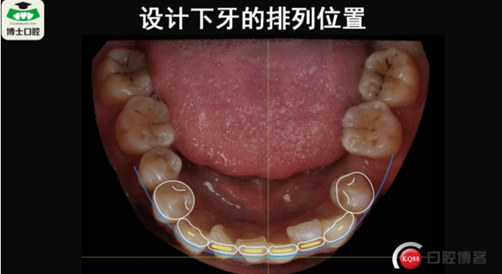

樹(shù)脂貼面與瓷貼面的孰是孰非~牙醫(yī)李強(qiáng)(濟(jì)南博士口腔)

樹(shù)脂貼面與瓷貼面的孰是孰非~牙醫(yī)李強(qiáng)(濟(jì)南博士口腔)

樹(shù)脂貼面與瓷貼面的孰是孰非~牙醫(yī)李強(qiáng)(濟(jì)南博士口腔)